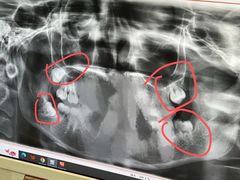

• 维乐口腔(格林门诊长宁店)

• -维乐口腔(格林门诊长宁店)